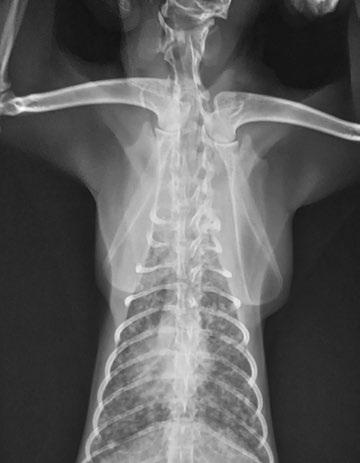

Columna vertebral

Como en abdomen, los parámetros serían alto miliamperaje y bajo kilovoltaje. Se puede colocar de forma laterolateral (figura 4) con los miembros anteriores estirados hacia craneal y los posteriores hacia caudal, o en posición ventrodorsal con el paciente en decúbito supino con los corvejones apoyados sobre la mesa. La columna vertebral debe quedar alineada con la mesa.

Figura 4. Proyección lateral de columna. Fractura de columna.